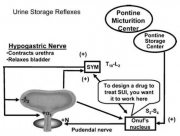

| 15:55, 2 באוגוסט 2014 | נוירוגנית2.png (קובץ) |  |

102 קילו־בייטים | Motyk | 1 | |